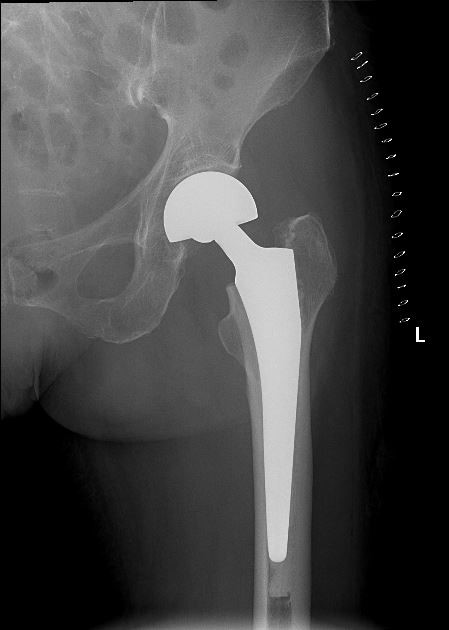

女   83岁

左侧股骨头置换术后

容积图像:

左侧股骨头置换术后复查

容积断层图像可以清晰显示置换的股骨头与髋臼的关系,也可以清晰显示植入物与股骨干之间的嵌合情况,为术后评估提供影像资料。